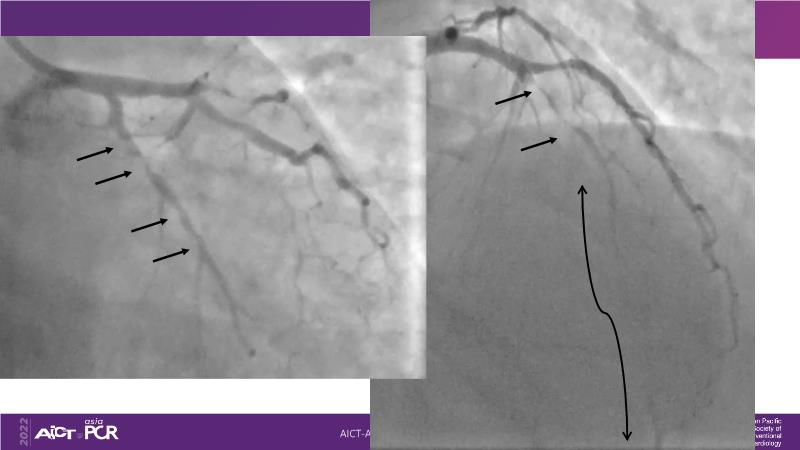

Sirolimus coated balloon: expanding the scope of coronary artery disease treatment

Consult this session to understand the technology and scientific evidence of the novel sirolimus drug-coated balloon, to learn its utility for PCI in a variety of lesion and patient subsets and to understand the evidence and outcomes in real-world patients.

- To learn the utility of the DCB for PCI in a variety of lesion and patient subsets

- To understand the evidence and outcomes of this DCB in real world patients